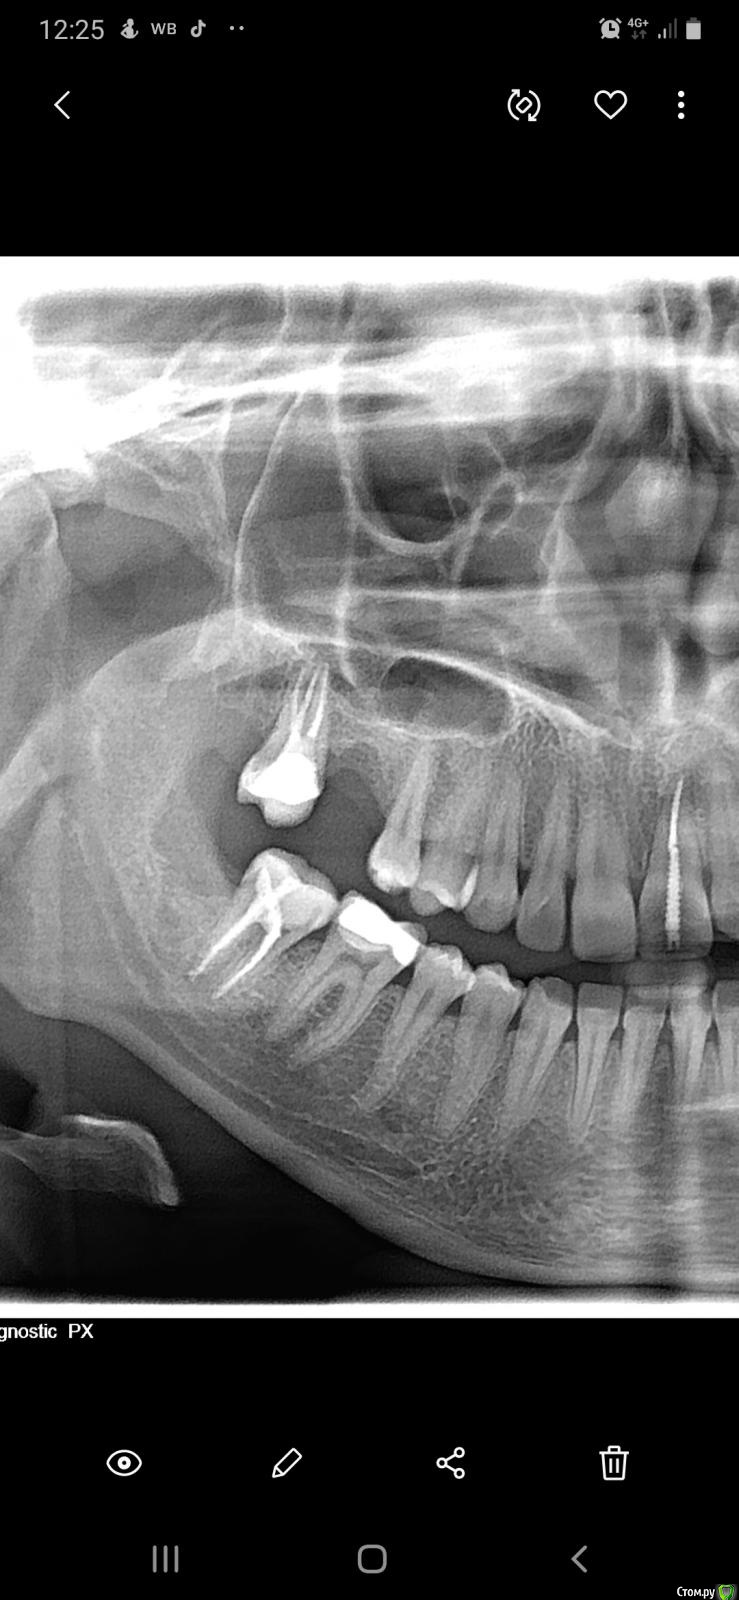

Аннушккка Опубликовано 28 февраля, 2020 Поделиться Опубликовано 28 февраля, 2020 (изменено) Болит внутри десна , и пятый зуб , но ничего не видно, на нижней челюсти, воспален подчелюстной лимфоузел снимок свежий) Изменено 28 февраля, 2020 пользователем Аннушккка Ссылка на комментарий

red_butler Опубликовано 28 февраля, 2020 Поделиться Опубликовано 28 февраля, 2020 Я бы в первую очередь смотрел 4.6 зуб Ссылка на комментарий

krokomot Опубликовано 29 февраля, 2020 Поделиться Опубликовано 29 февраля, 2020 проверить на витальность 4.6, и 4.7 не внушает доверия в плане пломбировки каналов, сделайте дополнительно томограмму. Ссылка на комментарий